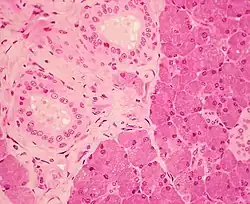

Stratified cuboidal epithelium in the ducts of the parotid gland, visible as the borders of the two circular structures in the upper left.

Stratified cuboidal epithelium, highlighting the nucleuses, the rest of the epithelial cells, and underlying connective tissue.